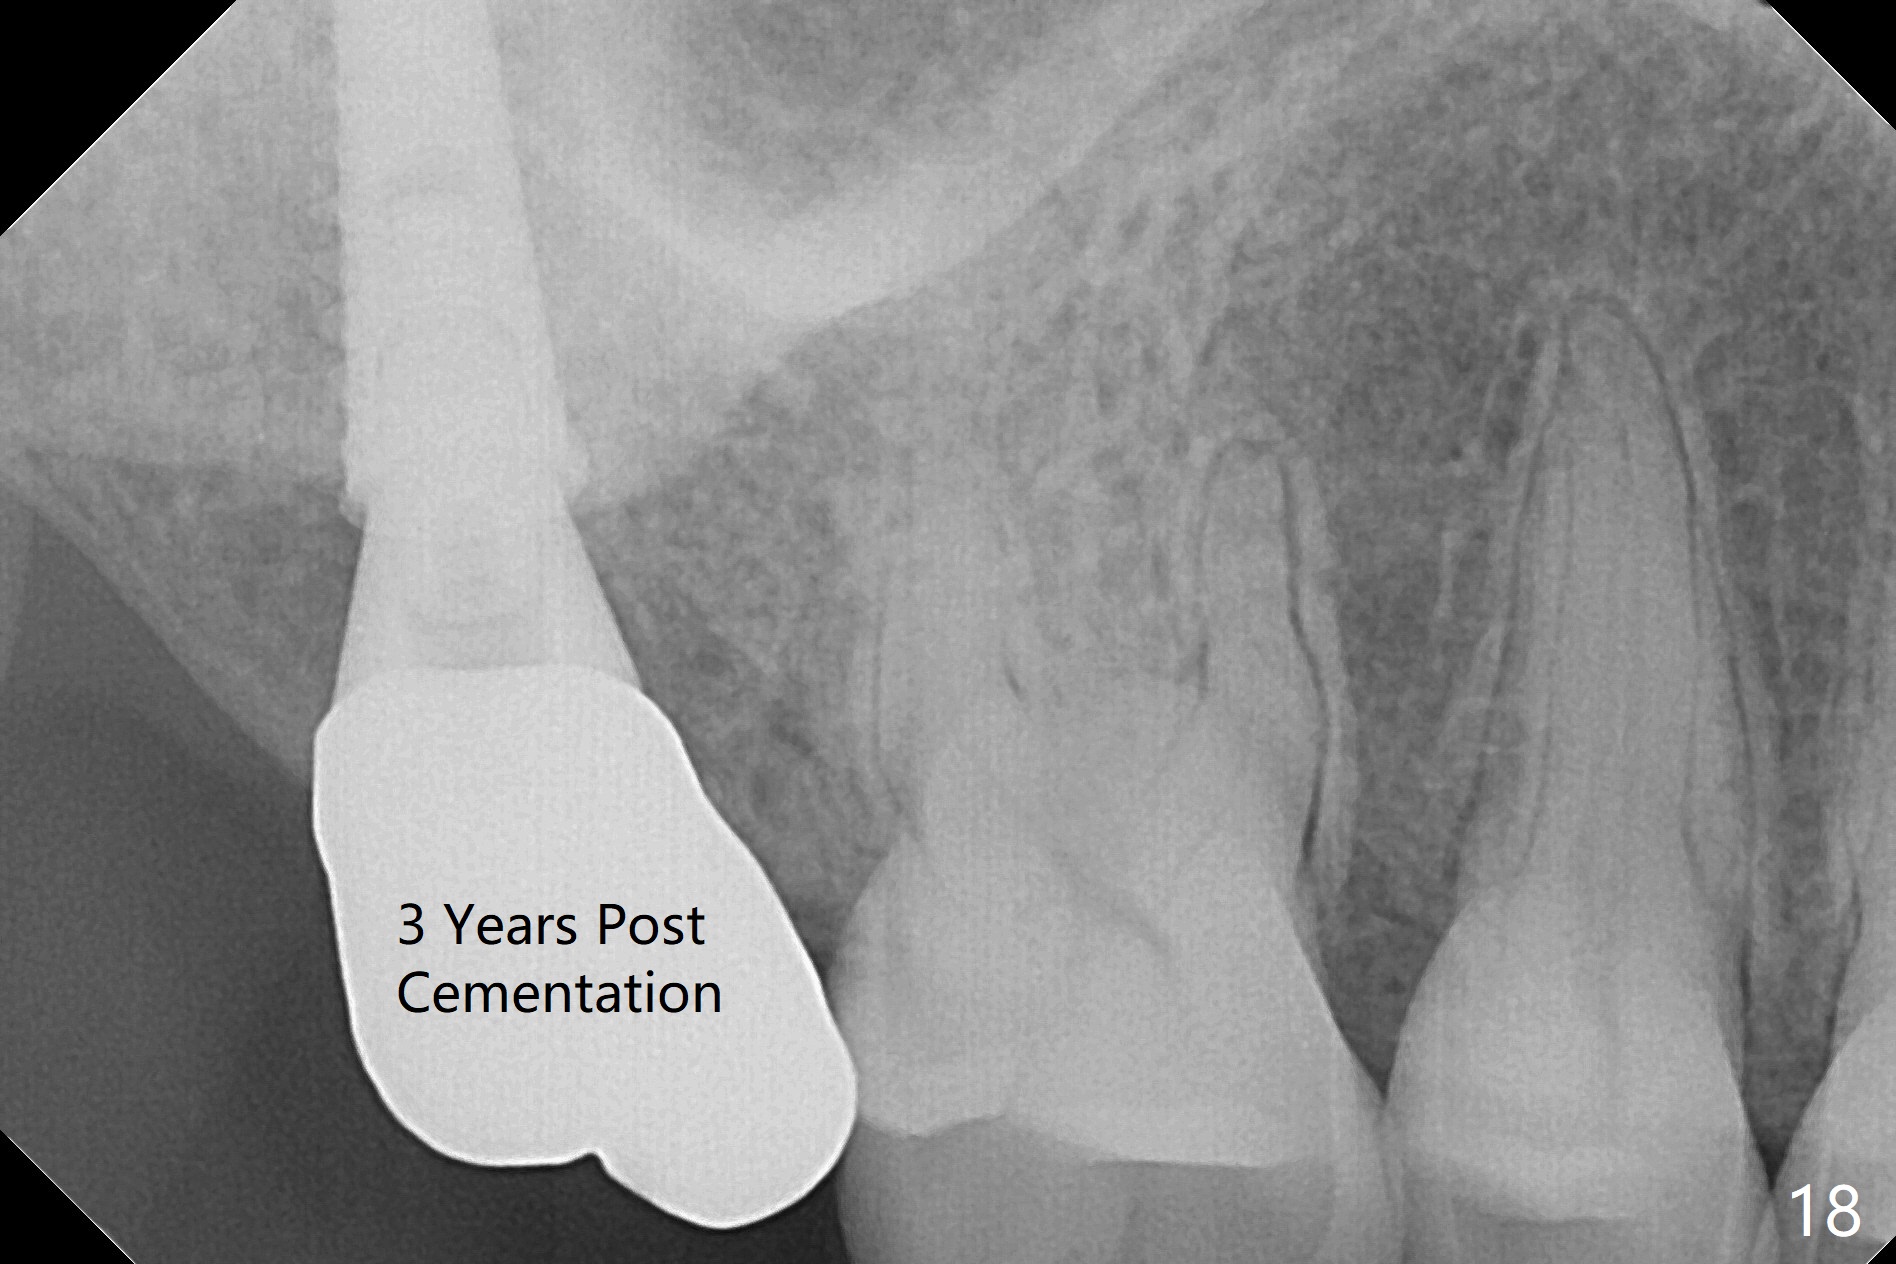

Fig.5 shows the mesial slope of the socket (M), which is more or less the center of the socket mesiodistally. If the osteotomy were set up in the red circle (Fig.6) in the mesial slope (Fig.8 green dashed line), the trajectory of 4.5x11 mm dummy implant (Fig.7) would be more ideal (Fig.8 red outline) with more native bone contact. Finally a longer IBS implant is placed (4.5x15 mm, Fig.9,10) to achieve primary stability (50 Ncm). When the provisional is removed for impression 3 months 10 days postop, the implant is found to have been placed distopalatally (Fig.13), which should have been avoided. It appears essential to use guide for a distal implant. It is agonizing to re-encounter the off-axial implant (Fig.14) and the distopalatal access hole (Fig.15) 1 year post cementation. It is also amazing that the abutment screw has not loosened. A fair-sized piece of bone graft has just been removed buccally (Fig.15,16). The patient complains of sensitivity 2 years 3 months post cementation, although there is no abnormality around the implant crown. Guided surgery is essential to avoid restoration complication. There is no thread exposure nearly 3 years post cementation; in fact the apical portion of the abutment is covered by the bone (Fig.17,18).